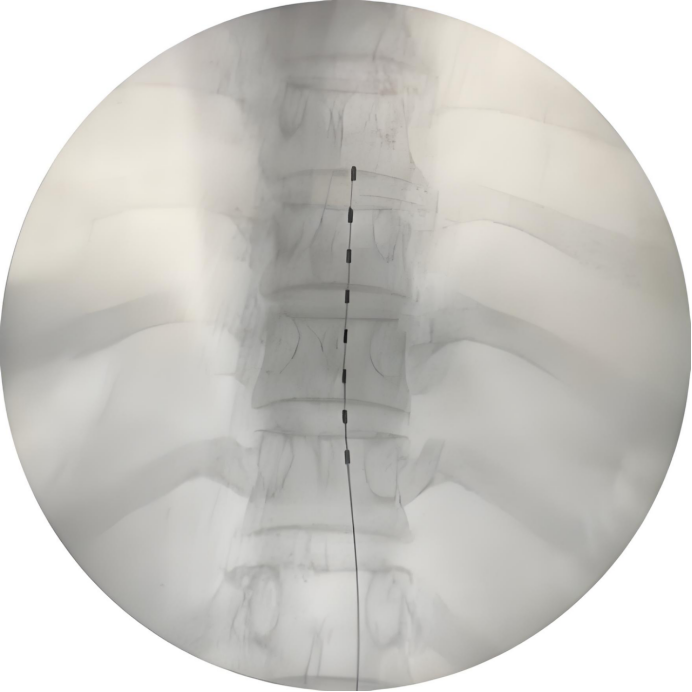

脊髓电刺激: 将电极植入椎管内硬膜外腔,释放微弱电流干扰或阻断疼痛信号上传至大脑。适用于药物和常规介入治疗效果不佳的顽固性PHN。